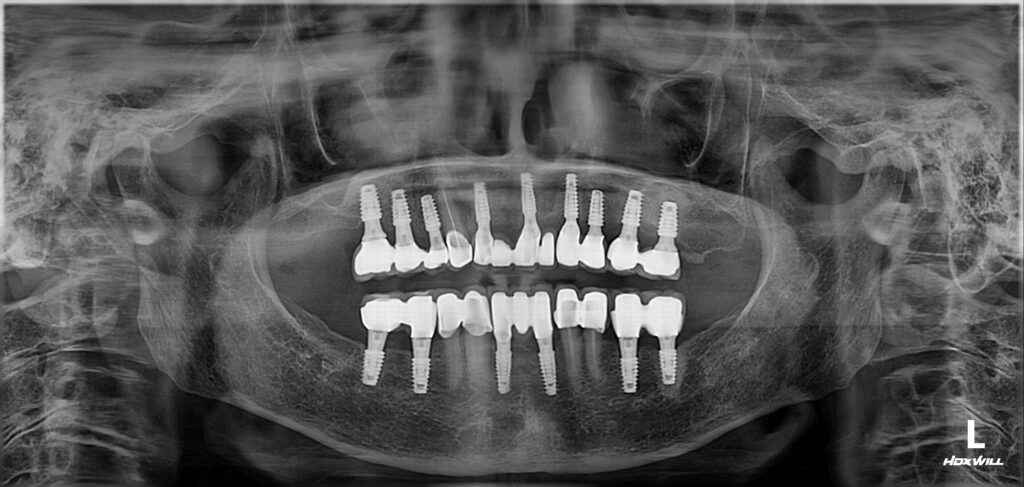

✔️ 오늘은 정왕동치과에서 가이드를 통한 전체 임플란트를 진행하신 환자분의 증례를 소개해 드리려고 합니다.

위 환자분께서는 지인분의 소개로 아드님이 먼저 치료를 받아보신 후 모시고 함께 내원하셨는데요. 타 치과에서 부분 틀니를 제작하였으나 적응을 하지 못하시고 빼고 지내신지 오래되셨다는 말씀을 해주셨습니다. 거의 식사를 잘 못하시며 지내시던 중 앞니까지 흔들리면서 치료받기를 희망하셨는데요.

고령이신 환자분께서는 치조골 소실이 심하셨는데요. 틀니 사용은 도저히 못하시겠다고 하셔서 임플란트로 진행하기로 하셨고 많은 양의 뼈이식을 동반하셔야 함을 설명드렸습니다.

환자분께서는 겁도 많으셔서 수술에 대한 두려움이 있으셨는데요. 따라서 가이드를 이용한 네비게이션 임플란트로 계획을 수립하였습니다.

3D CT 촬영을 총해 가이드를 제작하여 장착한 모습인데요. 여러 개의 임플란트를 동시에 식립해야 하는 경우에도 계획을 통해 한 번에 진행할 수 있어 전체적인 치료 기간을 단축할 수 있다는 장점도 가지고 있습니다.

이어서 순차적으로 임플란트 식립과 보철의 과정을 마무리하였습니다.

인공치근을 잇몸뼈에 식립한 후 기존의 잇몸뼈와 단단히 융합될 수 있는 기간을 충분히 기다려준 뒤 수치가 충분한 부위부터 차례로 마무리를 진행하였습니다.

환자분께서는 보험 임플란트 적용 대상자 셔서 앞니 두 개는 보험 임플란트로 진행하셨으며 위쪽의 뼈가 약한 부분은 2차 수술의 과정까지 거친 뒤 튼튼하게 사용하실 수 있도록 마무리를 하였습니다.